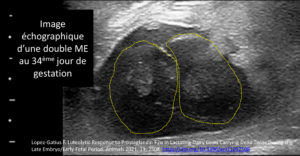

LA GEMELLITE UNILATERALE EST UNE AUTRE CAUSE D’AVORTEMENT

La émellité est une des principales causes d'avortement